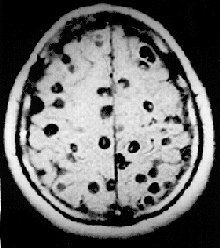

MRI brain scan: Neurocysticercosis

• Neurocysticercosis (NCC): is an infection of the brain or spinal cord caused by the larval stage of the pork tapeworm, Taenia solium. NCC is the most common helminthic (parasitic worm) infestation of the central nervous system worldwide. Humans develop cysticercosis when they ingest eggs of the pork tapeworm via contact with contaminated fecal matter or eating infected vegetables or undercooked pork.[37] "While cysticercosis is endemic in Latin America, it is an emerging disease with increased prevalence in the United States."[38] "The rate of depression in those with neurocysticercosis is higher than in the general population."[39]